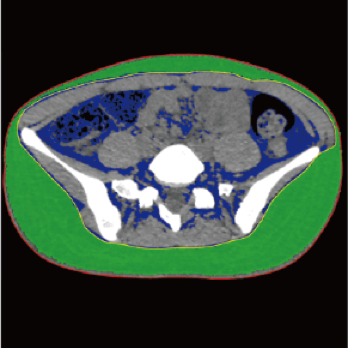

3 core components built on a new industry-leading configuration

Large-capacity tube delivers exceptional stability and durability, ensuring consistently high-quality output even under heavy workloads

High-power generator delivers high mA output for rapid scanning of complex anatomy and large coverage areas, boosting scan speed while enhancing image signal-to-noise ratio and minimizing artifacts

Wide detector expands single-rotation coverage, shortens exam time, reduces motion artifacts, decreases radiation dose, and saves tube exposure time while effectively lowering operating costs